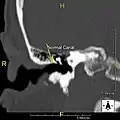

Exostosis in ear canal

The normal ear canal is approximately 7 mm in diameter and has a volume of approximately 0.8 ml (approximately one-sixth of a teaspoon).[5] As the condition progresses, the diameter narrows and can even close completely if untreated, although people generally seek help once the passage has constricted to 0.5–2 mm due to the noticeable hearing impairment. While not necessarily harmful in and of itself, constriction of the ear canal from these growths can trap debris, leading to painful and difficult to treat infections.